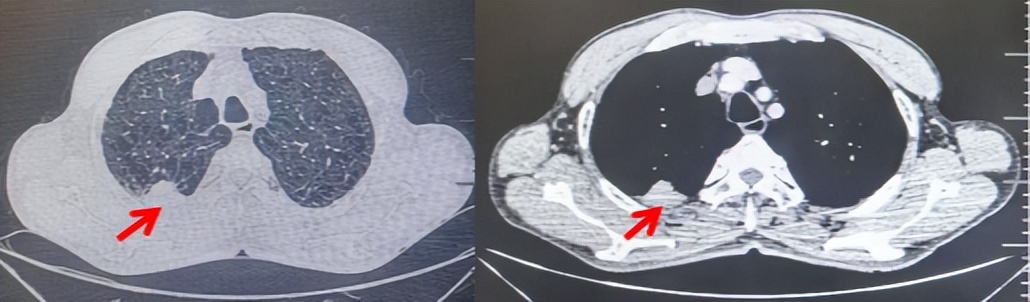

2024.11.19患者出现右侧胸痛,复查胸部CT检查示右侧胸膜肿物,大小约31mmX24mm,右侧4、5肋骨骨质破坏,考虑转移(如图2)。建议患者穿刺活检取病理明确诊断,患者拒绝,经MDT会诊后结合影像学表现及病史考虑为胸膜转移,肋骨转移,分期为rT0N0M1a IVA期,DFS仅仅17个月。2024.12.05起行信迪利单抗联合培美曲塞+卡铂方案治疗4周期,复查胸CT评效PR(如图3)。之后给予信迪利单抗+培美曲塞维持治疗6周期,期间复查CT评效PR(如图3)。目前信迪利单抗+培美曲塞维持治疗中,截止至目前PFS约为8个月,治疗期间未出现明显毒副反应。

图2:患者胸膜及肋骨转移(2024.11)胸部CT肺窗、纵隔窗及骨窗